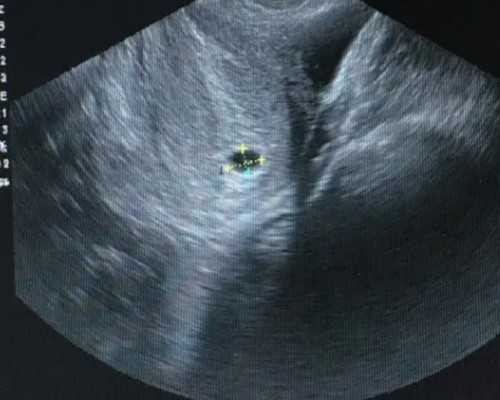

孕期胎儿脑积水是一种常见的胎儿神经系统疾病,及时识别并及时治疗是控制疾病发展的重要举措。准备怀孕和正在怀孕的妈妈,应该关注胎儿的发育情况,定期复查,及时发现胎儿脑积水的症状,并及时进行治疗。如果有发现异常情况,应尽快就医,以免影响胎儿的发育。tips